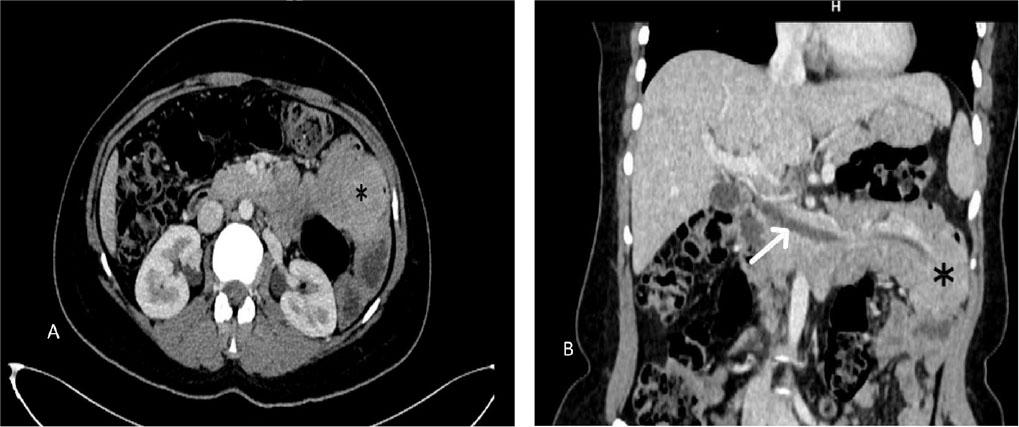

Figure 1.